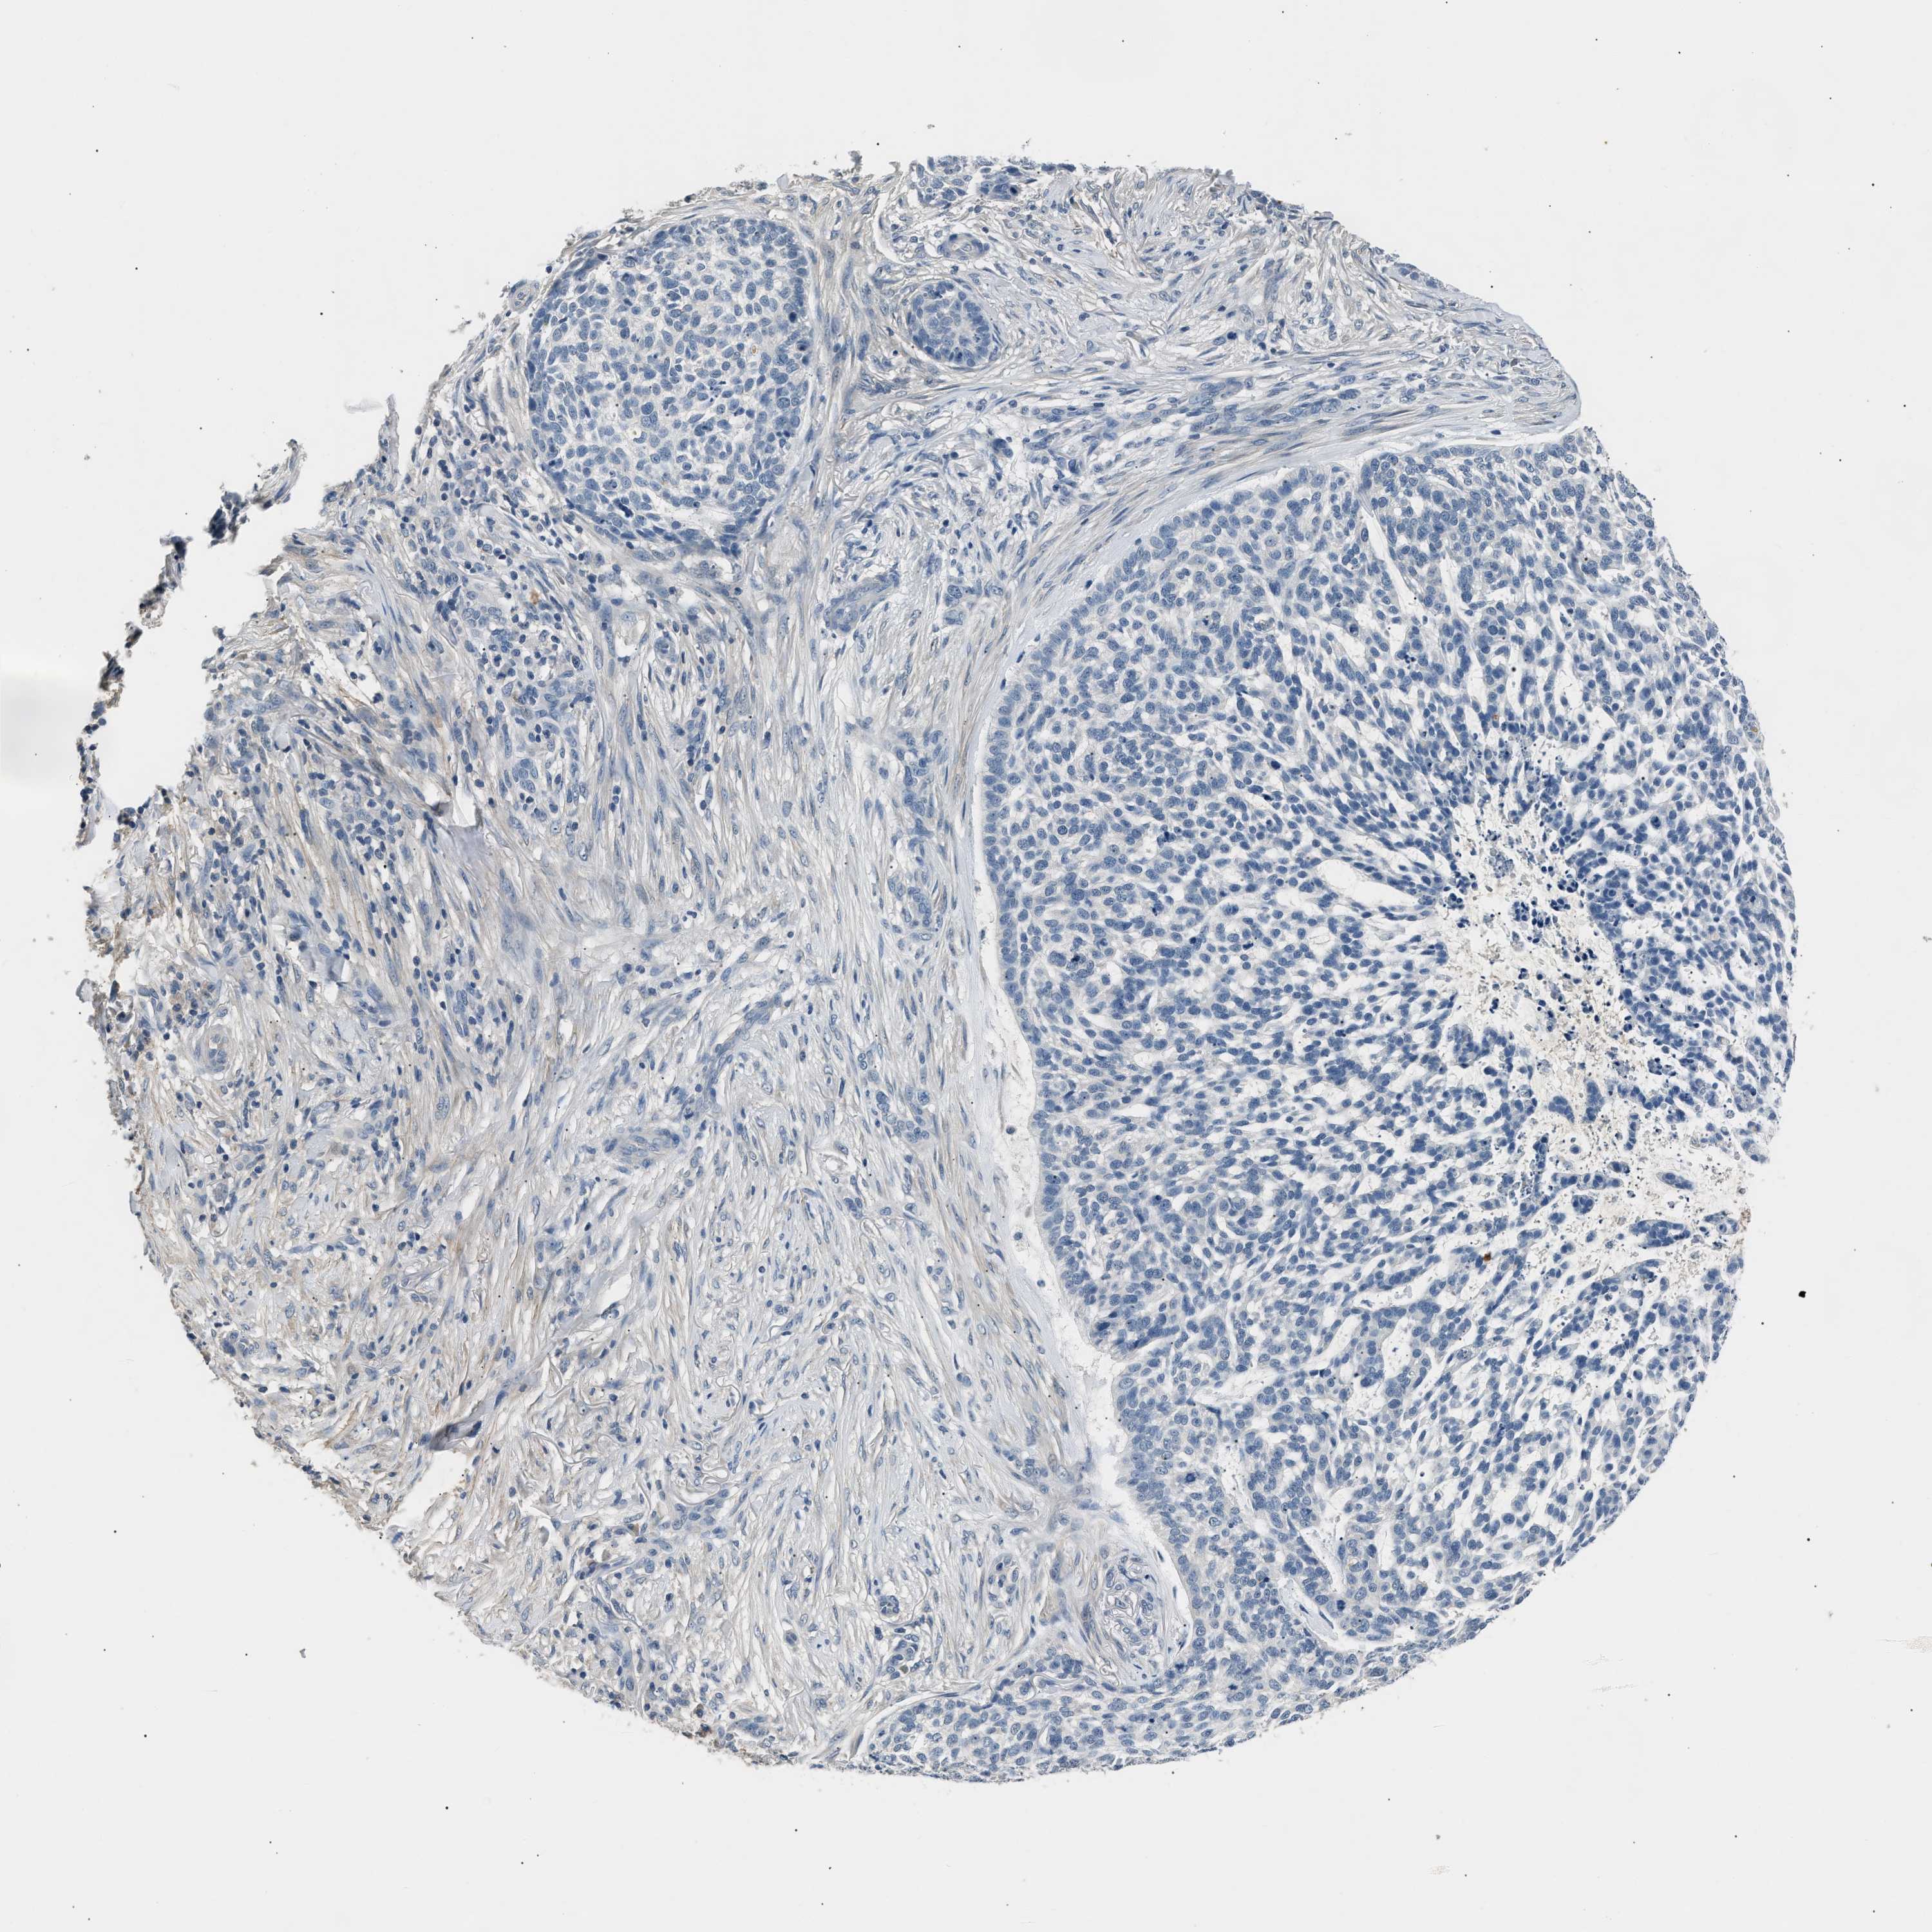

SKIN CANCER - Protein expressioni

A mouse-over function shows sample information and annotation data. Click on an image to view it in a full screen mode. Samples can be filtered based on level of antibody staining by selecting one or several of the following categories: high, medium, low and not detected. The assay and annotation is described here.

Antibody stainingi

Antibody staining in the annotated cell types in the current human tissue is reported as not detected, low, medium, or high, based on conventional immunohistochemistry profiling in selected tissues. This score is based on the combination of the staining intensity and fraction of stained cells.

Each image is clickable and will lead to virtual microscopy that enables deeper exploration of all samples and also displays staining intensity scores, fraction scores and subcellular localization as well as patient and tissue information for each sample.

Antibody HPA019141

Antibody CAB000047

Squamous cell carcinoma, NOS

Squamous cell carcinoma, metastatic, NOS